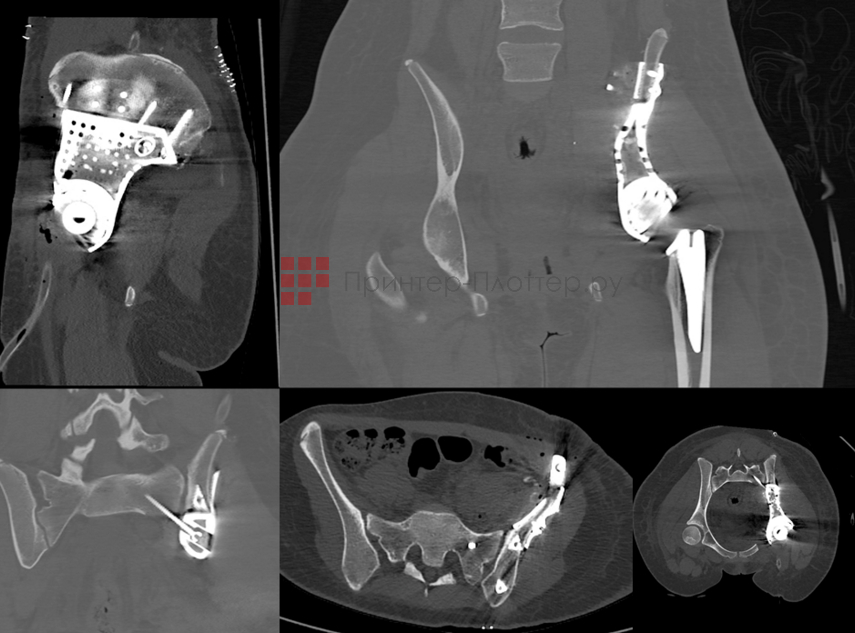

Медицина

Concept Laser M2 Series 5 используется для создания биосовместимых имплантов и протезов со специальной пористой поверхностью, для массового производства имплантов или медицинских компонентов, которые не могут быть изготовлены стандартным способом. Обеспечивает гибкость, позволяющую адаптировать имплантат к потребностям пациента, достичь желаемых механических свойств и облегчить хирургическое вмешательство.

Можно проектировать пористость, размер пор и взаимосвязь трабекулярных структур, чтобы обеспечить улучшенную первичную фиксацию и врастание кости. Позволяет создавать интегрированные трабекулярные структуры, которые снижают риск расслаивания и упрощают цепочку поставок, поскольку имплантат изготавливается за один этап и из одной детали.

Concept Laser M2 Series 5. Медицина